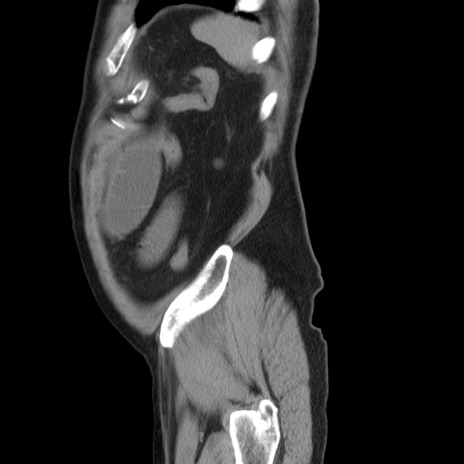

症例20(矢状断像)

【症例】 60歳代男性

【主訴】 腹部膨満、嘔吐

【現病歴】5日前頃より倦怠感を認め食事量減少し4日前の朝嘔吐、食事摂取困難となった。 3日前近医受診し点滴施行され整腸剤などを処方された。 当日他院を受診し、腹部膨満著明、炎症反応の上昇(CRP10.8、WBC11200)あり、紹介受診となる。

【身体所見】 意識JCS1 受け答えがはっきりしないBP 111/57mHg、 P 67bpm、、BT35.2°C、SpO2 97%(RA)、 腹部:膨隆、打診で鼓音あり、全体的に圧痛有り、腸蠕動音(-)、反跳痛ははっきりせず。

【データ】WBC 11400、CRP 14.20